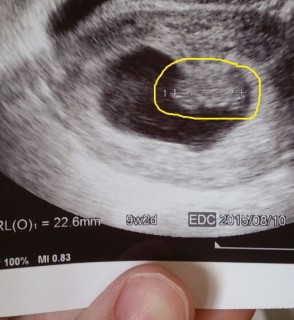

5週ですが既に22.6mmです!(大きい!) 先生からは9週くらいの大きさだね~気持ち大きめだね~ なんて言われましたが、順調のようで嬉しい!